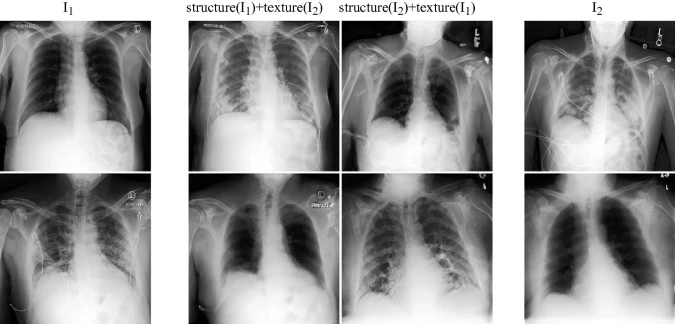

Lung Swapping Result. Two examples of lung swapping between images in column I1 and images in column I2. The Lung Swapping Autoencoder (LSAE) is able to successfully transfer target lung textures without affecting the lung shape. The swapping results are shown in the second and the third columns.